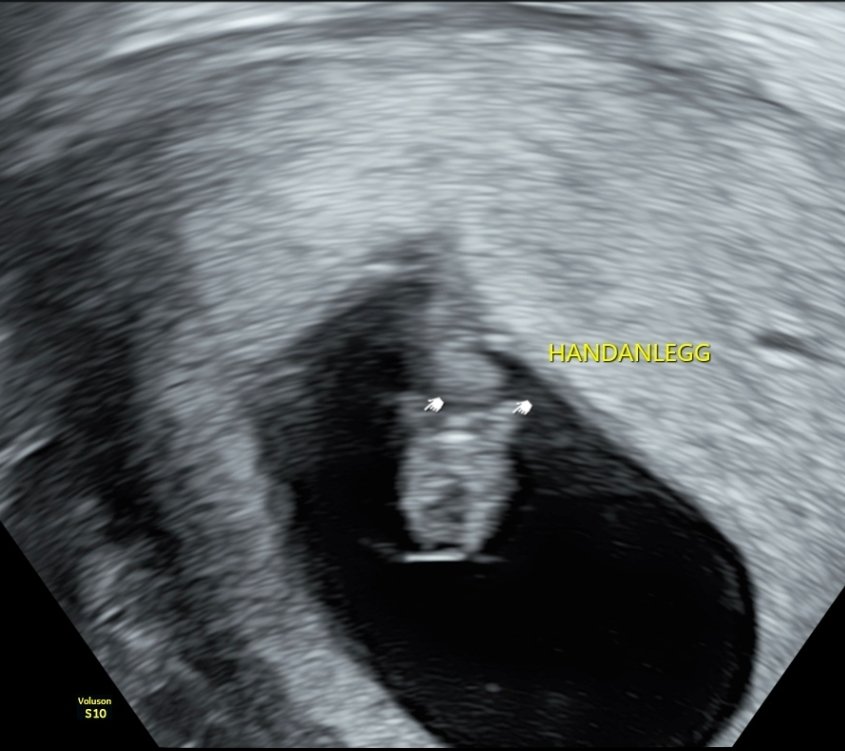

171 i hjertefrekvens og kunne se at navlestrengen pumpet, altså at morkaken for det meste iallfall har tatt over nåJeg er sååå glad! Men vi tørr fortsatt ikke fortelle det til noen da. Vi vil vente til nærmere uke 12

Embryoet ligger med hodet nedover på bildet.